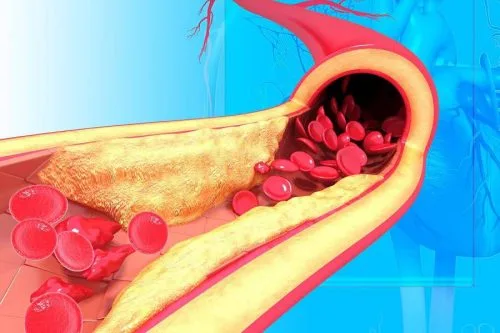

- گرفتگی رگ ها

- چربی خون بالا

- لخته خون